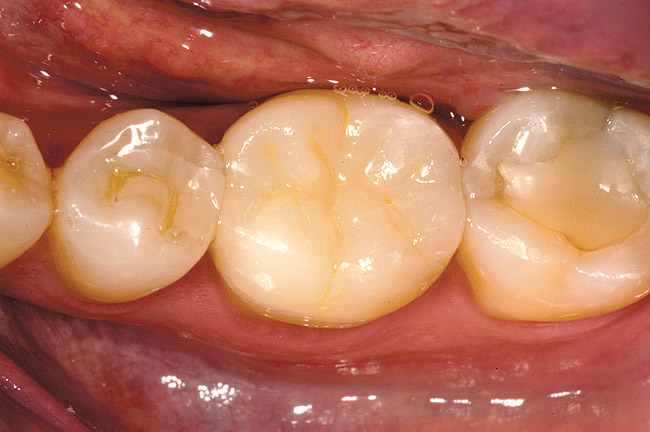

Figure 1a  A patient presents with large direct composite restorations and multiple crack lines in teeth Nos. 18 and 19. Tooth No. 19 was symptomatic to biting pressure.

Figure 1a

Figure 1b  The teeth were prepared for adhesively retained restorations. Note the significant ring of remaining enamel.

Figure 1b

Figure 1c  The final restorations restore and protect the compromised cusps.

Figure 1c

While in vitro studies do not definitively demonstrate a correlation between fracture resistance and cuspal coverage, cuspal coverage is still considered important in instances where the remaining tooth structure is less than one third to one half of the intercuspal distance.22,23 Other factors that support cuspal coverage of posterior teeth are the position of the tooth within the arch, with molars subject to greater bite forces and, therefore, exhibiting a greater need for cuspal coverage.24,25 Cracked teeth also warrant cuspal coverage (Figure 1A through Figure 1C).26,27